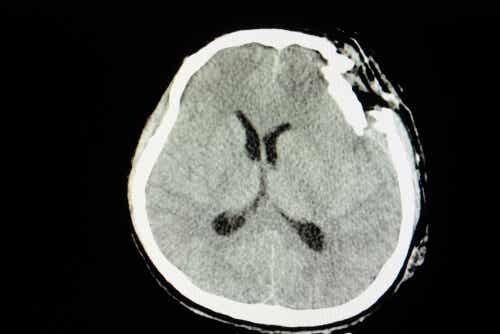

Un traumatisme crânien est un trouble neurologique résultant d’un coup violent. Tout comme nous pouvons nous blesser ou nous fracturer un bras lors d’un événement malheureux, nous pouvons également endommager la base de notre système nerveux. La seule différence est que compte tenu du type de dommage, les conséquences seront beaucoup plus graves.

Une inflammation résultant d’un coup n’est pas la même chose qu’une perte de masse encéphalique avec une fracture ouverte du crâne. De même, on peut dire que les principales séquelles sont évidentes au niveau cognitif, de la mémoire et de la personnalité.